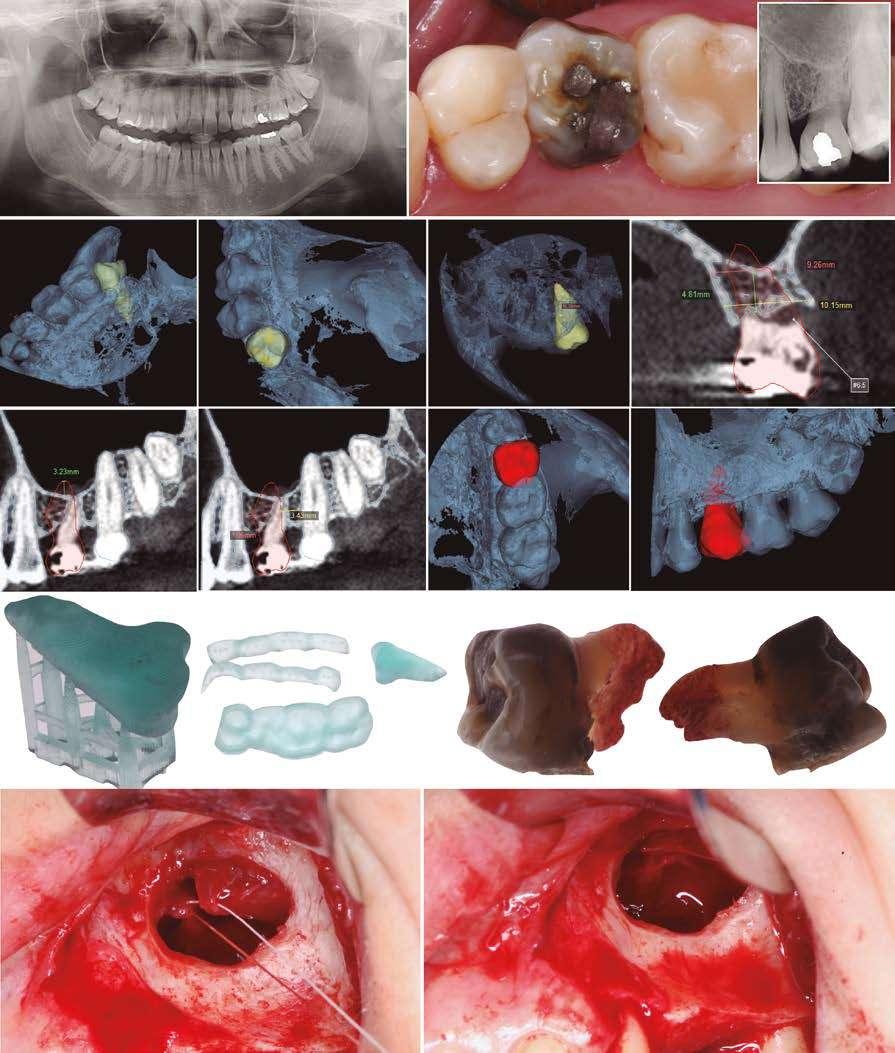

ELEVACIÓN TRANSCRESTAL CON IMPLANTES CORTOS UNITARIOS.

SERIE DE CASOS

Los implantes cortos y extracortos son una alternativa para las zonas de atrofia ósea alveolar a nivel posterior donde existe una altura reducida para la inserción directa de implantes de mayor longitud. En este caso la elevación de seno convencional o por abordaje lateral ha sido siempre la técnica a emplear hasta la llegada de estos implantes y la técnica de elevación transcrestal. A lo largo de este artículo se presentan una serie de casos con los que se concluye que los implantes unitarios cortos o extracortos, unidos a la técnica de elevación crestal, pueden ser una apuesta terapéutica segura y predecible cuando se emplean protocolos cuidadosos de inserción y de rehabilitación protésica.

Figura 2. Imagen inicial del caso donde podemos observar un resto radicular en posición 26 que debe ser extraído para posterior colocación de un implante dental.

Figuras 3 y 4 . Corte del Cone-beam dental tras la exodoncia y regeneración del alveolo con Endoret-PRGF cuatro semanas después. Podemos observar la atrofia ósea en sentido vertical de la zona con una altura máxima de 3 mm. La planificación como podemos visualizar será para la realización de una elevación transcrestal mínima y la colocación de un implante extracorto.

Figuras 5 y 6. Inicio de fresado de la cortical inferior del seno maxilar con la fresa de corte frontal.

Figuras 7 y 8. Despegamiento de la membrana para comenzar la elevación transcrestal.

Figuras 9 y 10. Inserción de membrana de fibrina como material de relleno en el neo-alveolo y colocación del implante.

Figura 11. Colocación de la corona con el transepitelial unitario 6 meses tras la cirugía.

Figura 12. Mantenimiento de la altura ósea lograda y de la estabilidad del implante al año de carga visualizada en cone-beam.

Figura 13. Estabilidad del tratamiento a los 7 años. No existe pérdida ósea asociada ni problemas relacionados con la prótesis.